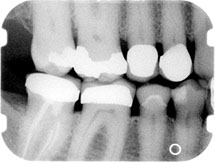

Before/After Photos